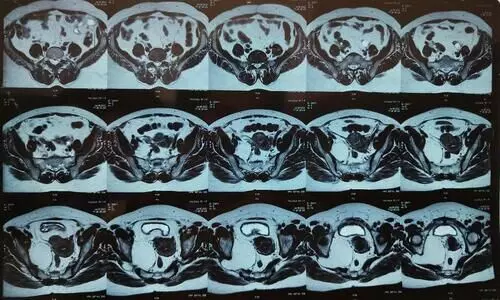

കാഞ്ഞിരപ്പള്ളി: 70കാരിയുടെ വയറ്റിൽനിന്ന് ആറ് കിലോയോളം വരുന്ന മുഴ നീക്കംചെയ്തു. കാഞ്ഞിരപ്പള്ളി ജനറല് ആശുപത്രിയിലെ...

തിരുവനന്തപുരം: എസ്.എ.ടി ആശുപത്രിയിൽ സങ്കീർണ ശസ്ത്രക്രിയയിലൂടെ രോഗിയുടെ വയറ്റിൽനിന്ന്...

തൊടുപുഴ: മധ്യവയസ്കയുടെ അണ്ഡാശയത്തിൽനിന്ന് 20 കിലോയുള്ള മുഴ നീക്കം െചയ്തു. ഇടുക്കി...

തിരുവനന്തപുരം: എസ്.എ.ടിയിൽ നടന്ന ശസ്ത്രക്രിയയിൽ 64 വയസ്സുകാരിയുടെ വയറ്റിൽനിന്ന് എട്ടുകിലോ തൂക്കമുള്ള മുഴ നീക്കം ചെയ്തു....